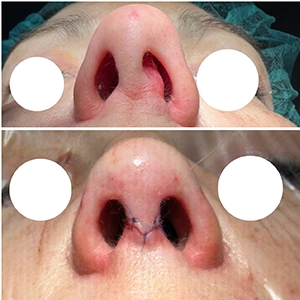

🎯 انتخاب بهترین جراح بینی در تهران

اگر به دنبال بهترین جراح بینی در تهران هستید، تجربه، نمونه کارهای موفق، ارتباط حرفهای با بیمار و آشنایی با تکنیکهای مدرن جراحی، معیارهایی مهم برای انتخاب شما هستند. حتماً عکسهای قبل و بعد عمل بینی بیماران را ببینید و در جلسه مشاوره تمام انتظارات خود را مطرح کنید.